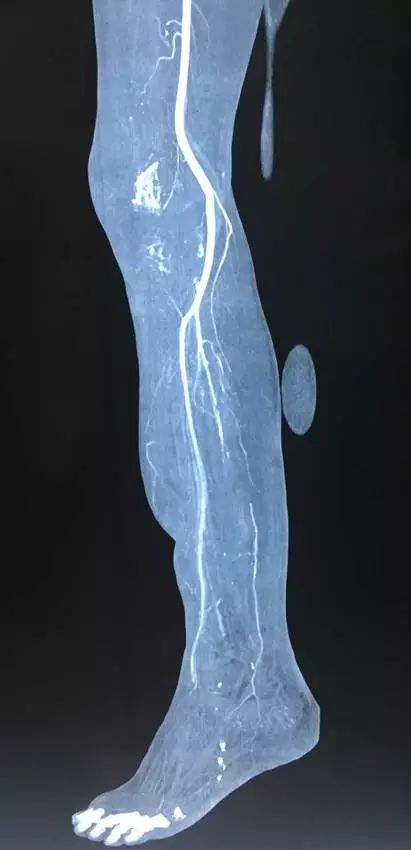

(网友提供)最后的病例是伤后40天由外地转来。开放骨折外固定架固定,骨坏死外露,用连珠和双氧水冲洗。入院时还存在足下垂,腓神经损伤、胫后动脉损伤。

• 接收该患者后第一次手术  清除病灶去除死骨27cm

• 抗生素骨水泥填塞。远端整块水泥包裹外露骨质,近端连珠以便骨搬移

• 钢丝克氏针张力牵拉皮肤,缩小创面

• 5天后下地部分负重走路

• 联合骨牵引纠正足下垂,5天后足下垂纠正后去除跟骨骨牵引针,保留胫跖骨牵引维持足于功能位。

• 而后行骨搬移、半开放植骨(如下)

• 第一次的骨水泥于80天后去除,行半开放植骨(植骨表面覆盖抗生素骨水泥)

• 因为有皮肤缺损,用骨水泥做成瓦片闭合伤口=半开放植骨

• 自体优质松质骨(如图)

• 皮肤采用了钢丝牵张闭合

• 骨搬移+半开放植骨=治疗缺损

• 植骨后一个月去除瓦片骨水泥,创面新鲜

• 钢丝克氏针张力闭合伤口加游离植皮

• 继续骨搬移

• 修整

• 入院6个月腓总神经恢复,胫前动脉再通

• 总的治疗过程2年基本完全康复